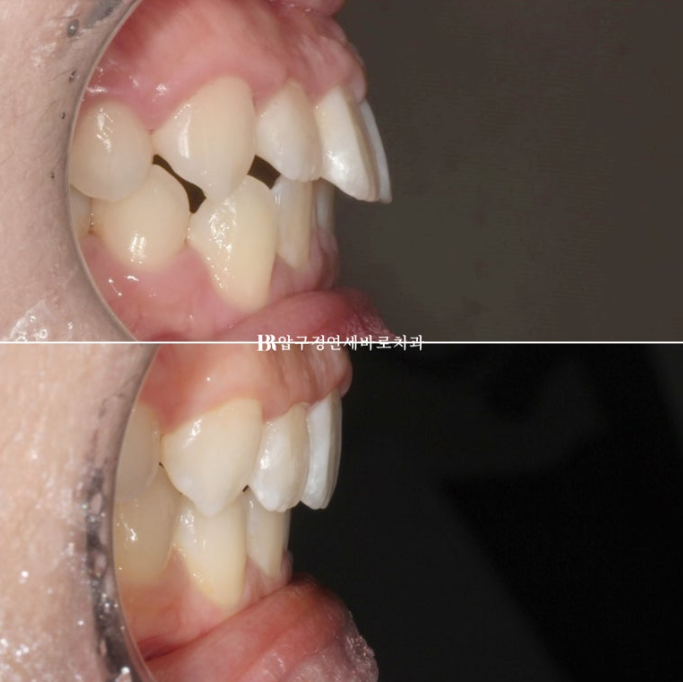

23.07-24.04

순서대로 23.07 초진 - 23.11 1차세트 후 재제작 - 24.04 치료 종료

총 치료기간은 중간에 장치 주문 후 기다리는 시간을 제외하면 실제 8개월 입니다.

치간삭제로 윗니 가운데 블랙트라이앵글도 없어졌습니다.